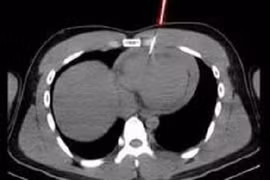

Đang làm việc với máy bắn đinh, nam thanh niên 21 tuổi vô tình trượt tay khiến một chiếc đinh bật ngược vào ngực. Ngay sau đó, nạn nhân cảm thấy đau dữ dội phải nhập viện.

Đang làm việc với máy bắn đinh, nam thanh niên 21 tuổi vô tình trượt tay khiến một chiếc đinh bật ngược vào ngực. Ngay sau đó, nam thanh niên cảm thấy đau dữ dội nên đến bệnh viện để sơ cứu.